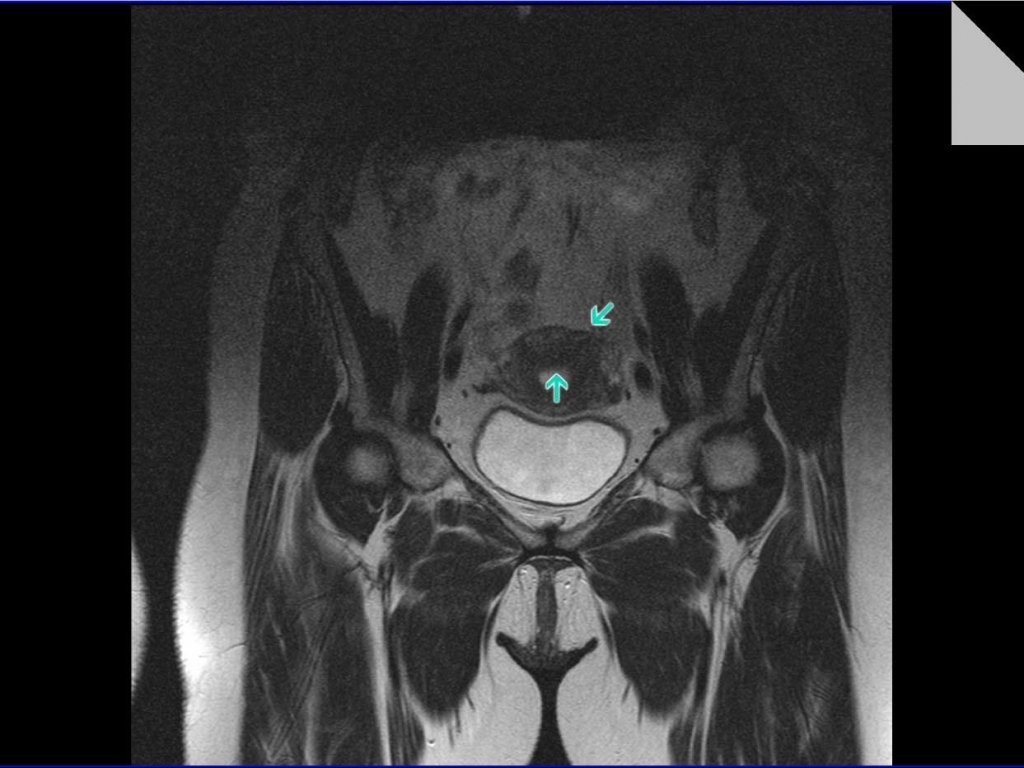

КТ-исследование абсцесса малого таза: Визуализация и диагностика

Раздел: Фотоальбом решений